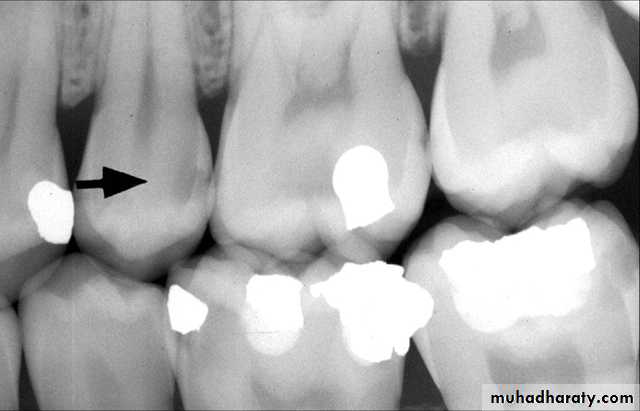

Radiograph of recurrent caries. This radiograph shows (1) radiolucent caries under the metallic restoration

Dental Recurrent Caries